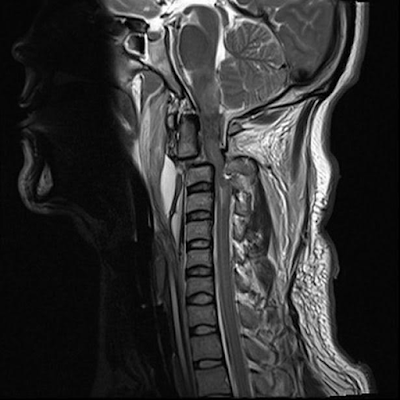

A man whose head was ripped from his spine in a horrific car accident surprised doctors by surviving for two years and went on to marry his heartthrob 4 days before his life support was switched off. Tony Cowan, 31, was involved in a car accident on September 9, 2014, which left him with a neck injury that doctors said was ‘unsurvivable’.